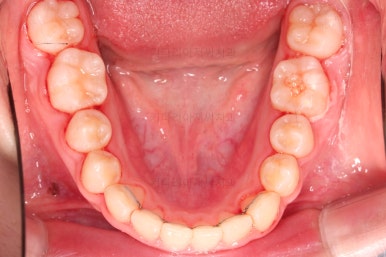

장치를 처음 부착한 사진입니다.

이번 환자분은 특징적으로 윗니의 장치와 아랫니의 장치가 다르죠.

윗니는 좀 더 심미적인 세라믹으로 선택하셨고 아랫니는 비교적 저렴하고 부피가 약간 작고 튼튼한 메탈로 진행했습니다.

덧니도 개선되었고 가지런한 느낌도 좋네요.

교합도 좋고, 평행하지 않던 느낌도 많이 좋아졌습니다.